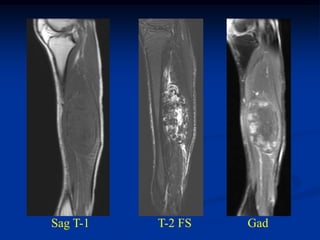

Case #261.1

55 yr female with enlarging and painful popliteal mass for 5 mos

Sag T-1         T-2

Gad

Axial T-1    T-2 FS

Cor T-1   T-2

Surgical resection